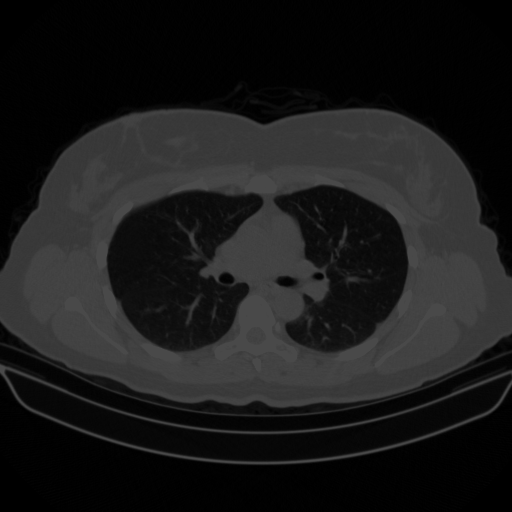

Original NATIVE CT scan (input)

Full window (WL 1023.5, WW 4095 β†’ Low βˆ’1024, High +3071)

Lung window (WL -600, WW 1500 β†’ Low βˆ’1350, High +150)

Mediastinum window (WL 40, WW 400 β†’ Low βˆ’160, High +240)